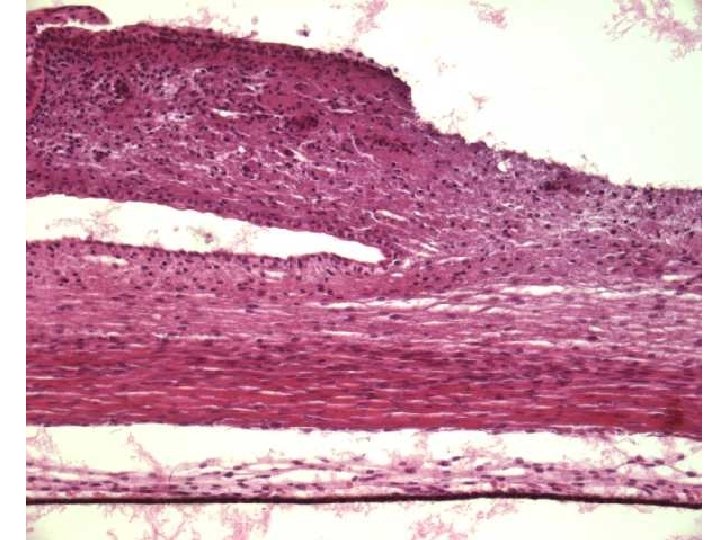

Tunica fibrosa (externa) Bělima = Sclera • 5/6 povrchu • neprůhledná vrstva hustého kolagenního vaziva a méně četných elastických vláken a fibroblastů • tloušťka: 0, 4 mm (kolem rovníku) → 1 mm (dorzálně) • do vnější vrstvy se upínají šlachy 6 okohybných svalů • tvoří ochranný obal hlubších oddílů a pevnou oporu pro úpon šlach okohybných svalů

Tunica fibrosa (externa) Bělima = Sclera vrstvy bělimy: • lamina episcleralis – tenká vrstva řídkého vaziva spojuje oční kouli s vagina bulbi, obsahuje cévy • substantia propria sclerae – hustá síť silných kolagenních vláken • lamina fusca sclerae (= lamina suprachoroidea) – fibroblasty a melanocyty

Rohovka – vrstvy 5 vrstev • epithelium anterius corneae – vícevrstevný dlaždicový nerohovějící epitel • lamina limitans anterior – Bowmanova membrána • substantia propria corneae • lamina limitans posterior – Descemetova membrán • epithelium posterius corneae – jednovrstevný plochý

Rohovka – vrstvy Epithelium anterius corneae • vícevrstevný dlaždicový nerohovějící epitel – obvykle 5 vrstev, 70 µm • velká regenerační schopnost (6 -denní cyklus), na okrajích dendritické Langerhansovy buňky • volná nervová zakončení v předním epitelu – z větví n. V 1 • povrchová vrstva (stratum superficiale) – oploštělé buňky mají na apikální povrchu mikroklky • prostřední vrstva (stratum intermedium) – obsahuje buňky překrývajíc vždy dvě bazální buňky pod ní • bazální vrstva (stratum basale) – kubické buňky, jejich lamina basalis spojená hemidezmozómy s hlubší lamina limitans anterior

Rohovka – ostatní vrstvy • lamina limitans anterior Bowmani – hustá vrstva kolagenních vláken bez fibroblastů (12 µm) • substantia propria – 200 -250 vrstev uspořádaných kolagenních lamel, fibroblasty s větvenými výběžky, makrofágy, neutrofily a lymfocyty (500 μm) – rozptýlí jen 1 % procházejícího světla – poranění způsobí jizvu (zákal rohovky) • lamina limitans posterior Descemeti – silná bazální membrána zadního epitelu rohovky (3 -10 µm – zesiluje se s věkem)